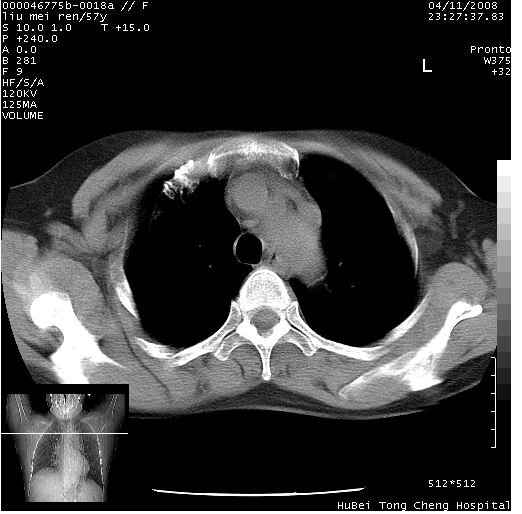

患者 女,57岁。因车祸受伤,其家属要求行“全身ct检查”。平素健康。

胸部ct轴位平扫(层厚10mm,螺距1.5,重建间隔10mm),图像如下:

左位上腔静脉,先天变异。

左位上腔静脉,先天变异。与双侧上腔静脉区别。